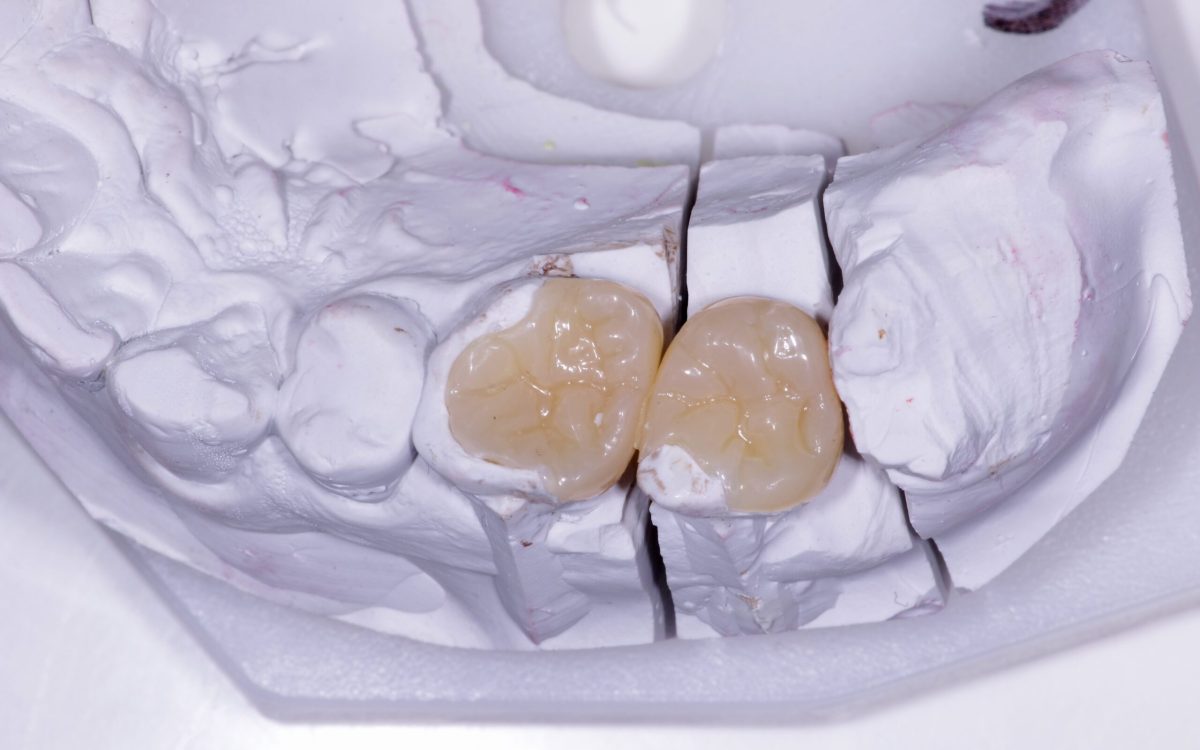

Fog betét (inlay, onlay)

A betét olyan, fogtechnikus által készített esztétikus fogpótlás, mely a fog koronai részén helyezkedik el mint egy nagyobb tömés és bizonyos esetekben nagyobb védelmet képes nyújtani, mint a fogtömés. Betéteket a kis-és nagyőrlő fogakra helyezhetünk! Élethű, strapabíró és megfelelő szájhigiénia mellett sokáig képes védeni a fogat.

Hogyan készül a fogászati betét?

Miután megállapítottuk, hogy tömés helyett betétre lesz szükség, lenyomatot veszünk. Ez alapján a fogtechnikus elkészíti a betétet, amit kb. egy hét múlva rögzíthetünk a fogra. Ezt a fogra próbálva még igazíthatjuk – pl. elvehetünk a magasságából, ha páciensünk így érzi kényelmesnek. A lenyomat és a kész betét közötti időre ideiglenes betétet helyezünk a fogba, hogy érzékenyésgét csökkentsük és stabilitását megpróbáljuk a végleges pótlás érkezéséig megóvni.

Milyen anyagú fog betétek léteznek?